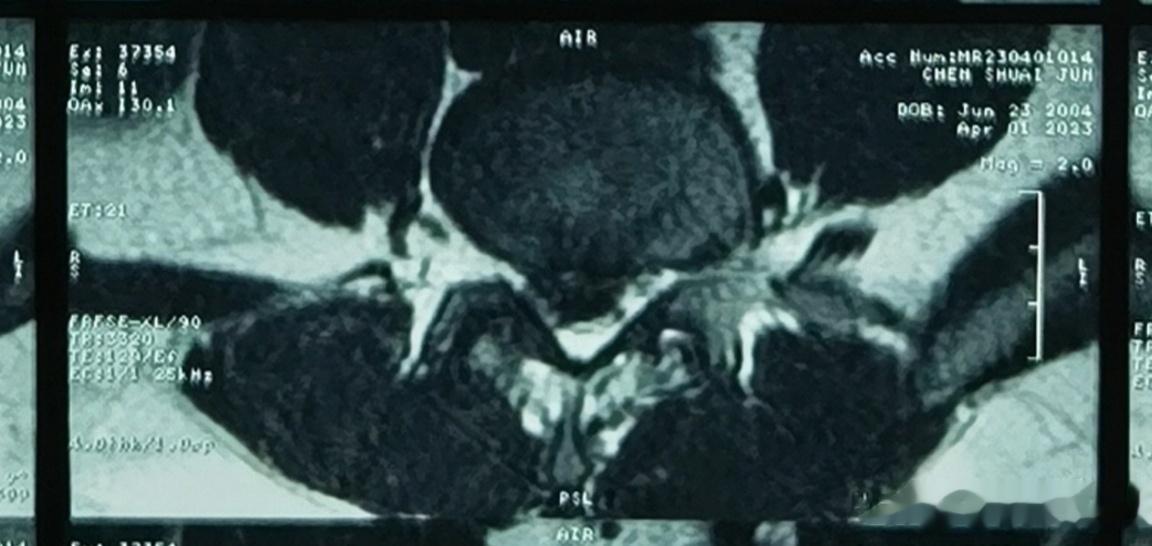

可怜的小胖孩子,一个喷嚏把自己打废了。椎间盘突出这么多,18岁大男孩,疼的哭😭。做了微创手术,再做阳光快乐大男孩。